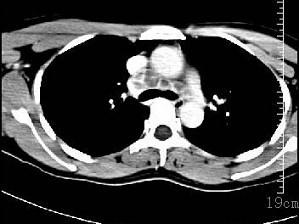

问题 女性35岁,发热、盗汗近3个月,颈部摸到多个结节,CT扫描如图所示,请选择最可能的诊断 ( )

选项 A、淋巴结核 B、淋巴瘤 C、结节病 D、淋巴转移癌 E、神经鞘瘤

答案 A